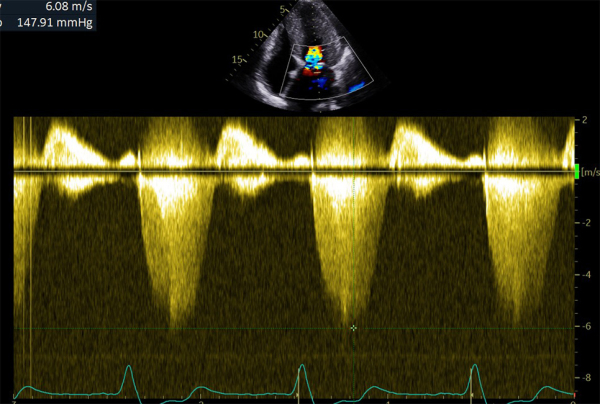

Figure 3 : flux Doppler continu trans-mitrale d’IM

Figure 4 : superposition des 2 flux Doppler continu d’obstruction sous aortique et d’IM

- Patient de 40 ans avec une CMH sarcomérique (mutation HTZ MYBPC3) avec épaisseur maximale en antéro-septo-basal à 33mm en IRM, associée à une obstruction sous aortique significative (GD max 77 mm Hg au Valsalva). Découverte d’une insuffisance mitrale (IM) sévère mixte organique sur prolapsus de P2 et fonctionnelle sur un SAM (mouvement systolique antérieur de la valve mitrale)